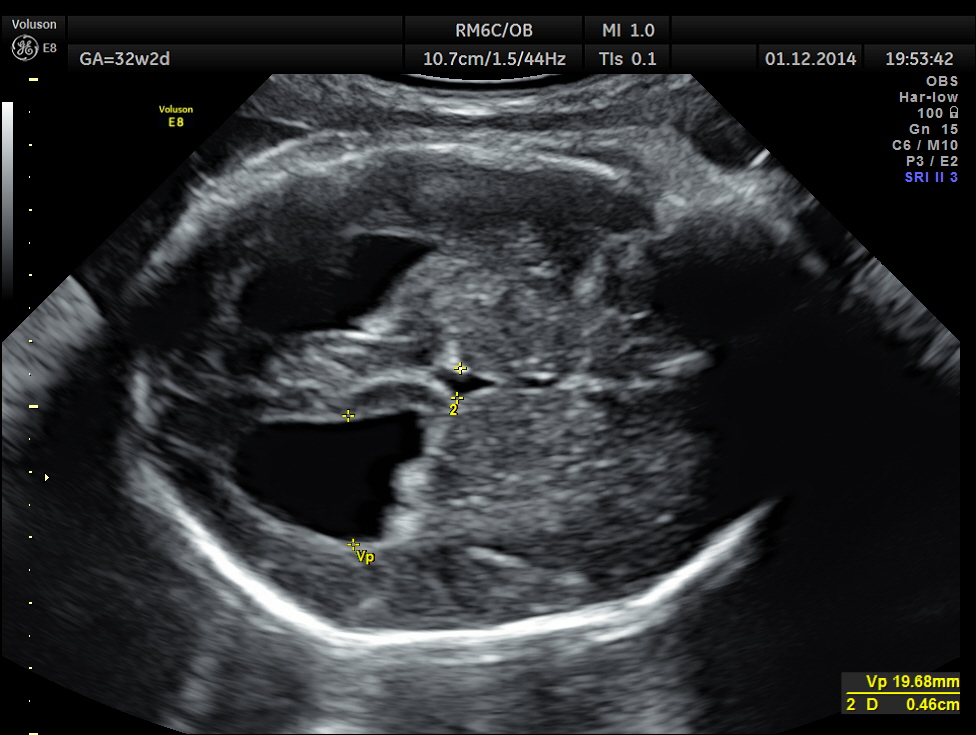

This was a 30 year old lady , with history of consanguinity ; 2nd gravida , 1st child normal ; she has never gone for an ultrasound examination in this pregnancy and was sent by her consultant to a different centre for evaluation . She was found to have hydrocephalus and was referred to our clinic for 2nd opinion.

The following images were obtained.

Hydrocephalus is seen ; Cisterna magna appeared somewhat compressed.